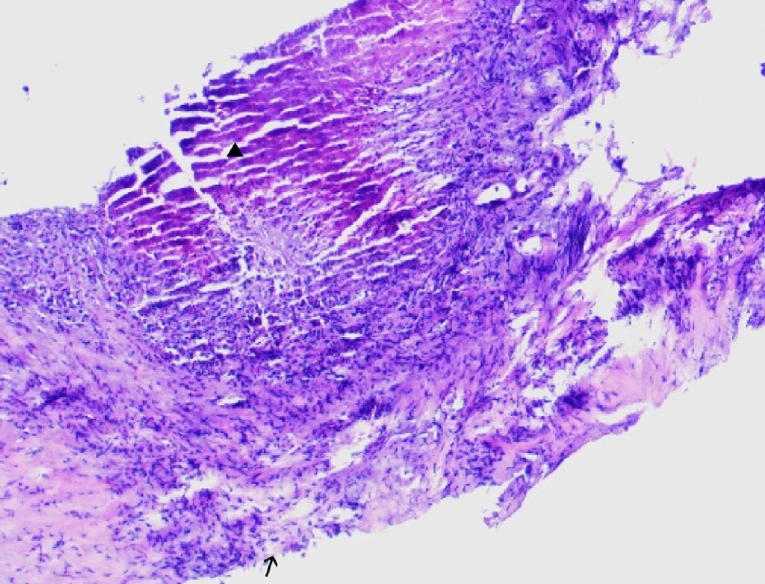

Postoperative pathology revealed features of alveolar echinococcosis, including extensive necrotic debris and peripheral palisading granulomatous inflammation with fibrosis (Fig. 5). The presence of a characteristic laminated layer was observed. The overall histopathological architecture, in conjunction with the clinical and radiological presentation, was highly consistent with HAE despite the absence of protoscoleces.

The definitive histological diagnosis of alveolar echinococcosis typically relies on the identification of parasitic structures, such as the laminated layer and protoscoleces within the lesion. In the present case, the pathological findings were highly suggestive of HAE, demonstrating the characteristic laminated layer and surrounding fibro-inflammatory response. However, the absence of observable protoscoleces on histopathology remains common, particularly in advanced cases where extensive necrosis and calcification may obscure parasitic elements, making it important to integrate pathological findings with serological, molecular, and imaging data for a conclusive diagnosis.

Fig. 5.

The histopathological examination reveals a characteristic laminated layer (▲), displaying a wavy eosinophilic structure. The germinal layer (→) shows hyperchromatic nuclei. Surrounding hepatic tissue exhibits inflammatory cell infiltration. H&E staining, ×400.

Fig. 5. The histopathological examination reveals a characteristic laminated layer (▲), displaying a wavy eosinophilic structure. The germinal layer (→) shows hyperchromatic nuclei. Surrounding hepatic tissue exhibits inflammatory cell infiltration. H&E staining, ×400.